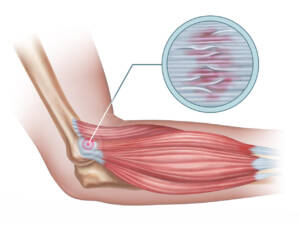

Ottima per disturbi muscolo scheletrici come ernia del disco, tunnel carpale,

gomito del tennista,

periartrite della spalla,

artrosi del ginocchio

e protursioni.